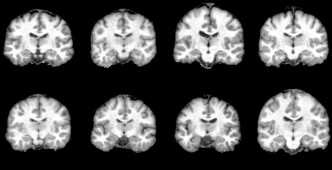

3D Brain MRIs We curate a dataset of about 27k datapoints for training with no diagnosed disease from the following datasets: ADNI petersen2010alzheimer , ABCD Study Karcher2021 ; Volkow2019 , HCP VANESSEN201362 , PPMI Pulliam2011 , and AIBL ELLIS2009672 . This task contains uncertainty in anatomical details such as ventricle sizes. Our setting employs demographic input conditions on age and binary sex (0: male, 1: female) and fine-tunes the Medical Open Network for Artificial Intelligence (MONAI) monai ’s optimized 3D LDM along with Rainbow training. We benchmark Rainbow against LDM and a GAN-based kwon2019braingan baselines. Rainbow’s graph generator module includes , , and .

Brain MRIs Figure 5 showcases the generated brain MRI images conditioned on a 65-year-old male individual. Unlike younger age groups (e.g. 10-20 years old) with characteristic small ventricles, or the older age groups (e.g. 70+ years old) with large ventricles alasar2019morphometric ; 10.1001/jamanetworkopen.2023.18153 ; 10.1001/archneur.60.7.989 , the 60s age range includes a wide variety of ventricle patterns raz2004aging , as visualized in Figure 5a with actual samples. While all models generated high-quality images, Rainbow effectively captures the diverse ventricle patterns with varying ventricle sizes, whereas the baseline LDM tends to produce similar ventricle regions across different samples. We provide full axial, coronal, and sagittal views for this experiment in Figure 28 and visibility of structures and details in generated 3D MRIs in Figure 27 in Appendix E.

In addition, we quantify brain MRI generations obtained from multiple tasks: image synthesis (with 200 conditions balanced on age and sex) and counterfactuals on age (three age shifts at 10, 40, and 80 years) and sex (flipping binary sex). For each task, we report FID score Seitzer2020FID and performance on age and sex prediction by pretrained classifier models (details at Appendix D.2). As shown in Table 1, Rainbow outperforms LDM and GAN baselines across all metrics and tasks with lower FID, higher sex accuracy, and lower age MAE. To justify age and sex prediction models, we report "Real" results that were tested on real data and "Random" results that were evaluated on random outputs. Figure 29 in Appendix E provides counterfactual generations.